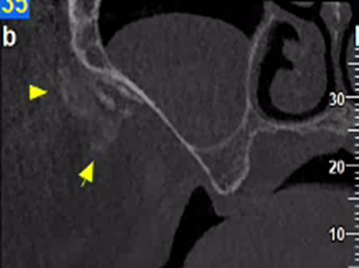

Εκτός από τις παραπάνω ελάχιστα επεμβατικές τεχνικές, στις απεικονίσεις της τραχηλοπροσωπικής χώρας μπορεί να συναντήσουμε και τα αποτελέσματα πιο επεμβατικών τεχνικών, όπως διάφορες μορφές πλαστικής χειρουργικής με χρήση ενθεμάτων σιλικόνης.

Ένα παράδειγμα είναι η γενειοπλαστική, όπως φαίνεται στην παρακάτω περίπτωση.